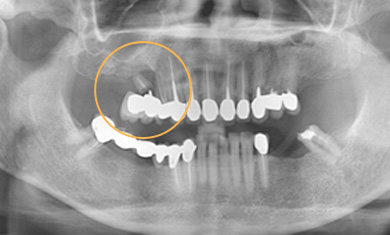

長牙橋導致蛀牙-案例一

拆下牙橋前

拆下牙橋後